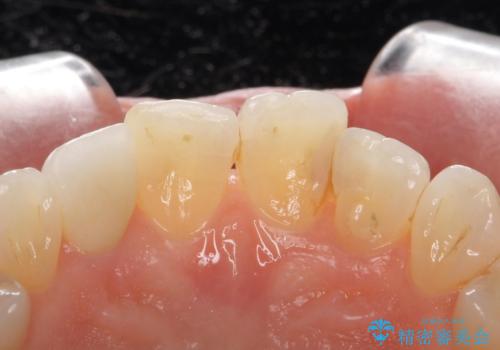

- 右上の前歯が取れたとのことで来院された患者様です。

再根管治療からのやり直しをご提案しましたが、ご希望されなかったため土台(コア)のやりかえからとなりました。